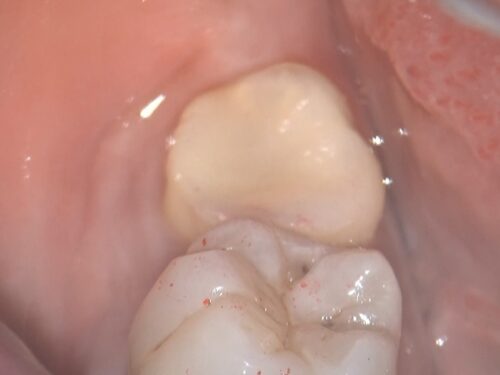

割れた破片を取り除いた直後の状態です。

骨の中まで割れていたことが確認できます。このような深い破折の場合、通常は抜歯が必要となります。

その2日後です。赤い円で囲んでいるのが抜歯予定の歯です。